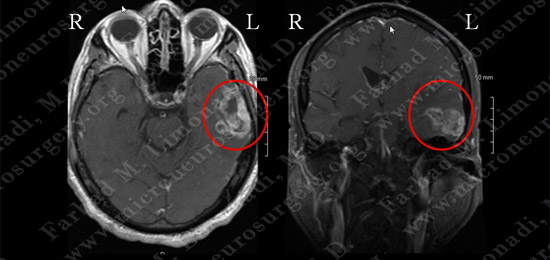

MRI scan of the patient’s brain showed a large left temporal brain tumor.